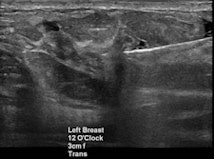

Mammography, ultrasound, and MRI each has its role in diagnosing suspicious lesions. But establishing the radiologic-pathologic correlation is just as important to ensure concordance -- and even that's not necessarily the end of the line for radiologists looking for optimal care, said Shaheen, who is acting chair of radiology and chief of women's imaging at Mafraq Hospital in Abu Dhabi, United Arab Emirates.

"We as the breast imagers are the major players in the multidisciplinary team in breast cancer management, or breast cancer in general, especially if the patient needs some imaging," Shaheen said. "We are consultants to clinicians to advise on what's the next best step, and we are experts on multimodality imaging and interventions including mammography, ultrasound elastography, MRI, core biopsy for fine-needle aspiration, and needle localization."

Breast cancer findings include masses, calcifications, developing asymmetry, and skin thickening, which is often imperceptible, Shaheen said. For whatever reason the patient is called back -- a finding on mammography, a clinical finding, or a patient discovering a symptom -- the diagnostic path generally begins with multimodality imaging, followed by image-guided biopsy. Then comes the critical rad-path correlation and, ultimately, assessment of cancer pathology and hormonal status before deciding on treatment, which greatly depends on the individual case.

Perhaps there are suspicious microcalcifications in a case of recurrent breast cancer. Should the patient undergo bilateral fine-needle aspiration or ultrasound-guided biopsy? Has lymph-node status been checked? Radiologists should measure not just the size of the lymph nodes but the thickness as well.